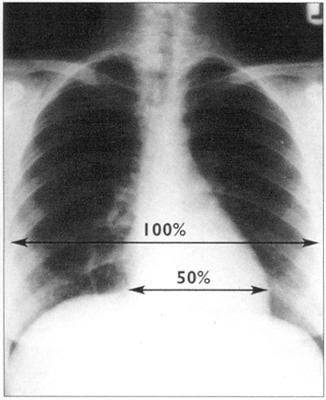

5.胸片

质量好的胸片既能看心脏的情况又能看清肺野。如图51正常的后前位片所示的心影。

图51 正常的后前位胸部×片

心胸比率能说明心脏大小。算法为心影的最大横径除以胸腔的最大横径,心胸比率只能在后前位上计算。正常情况下,其值应小于50%。左室和右房增大通常很容易鉴别,左房增大好像心缘又多出一个影,即双房影。